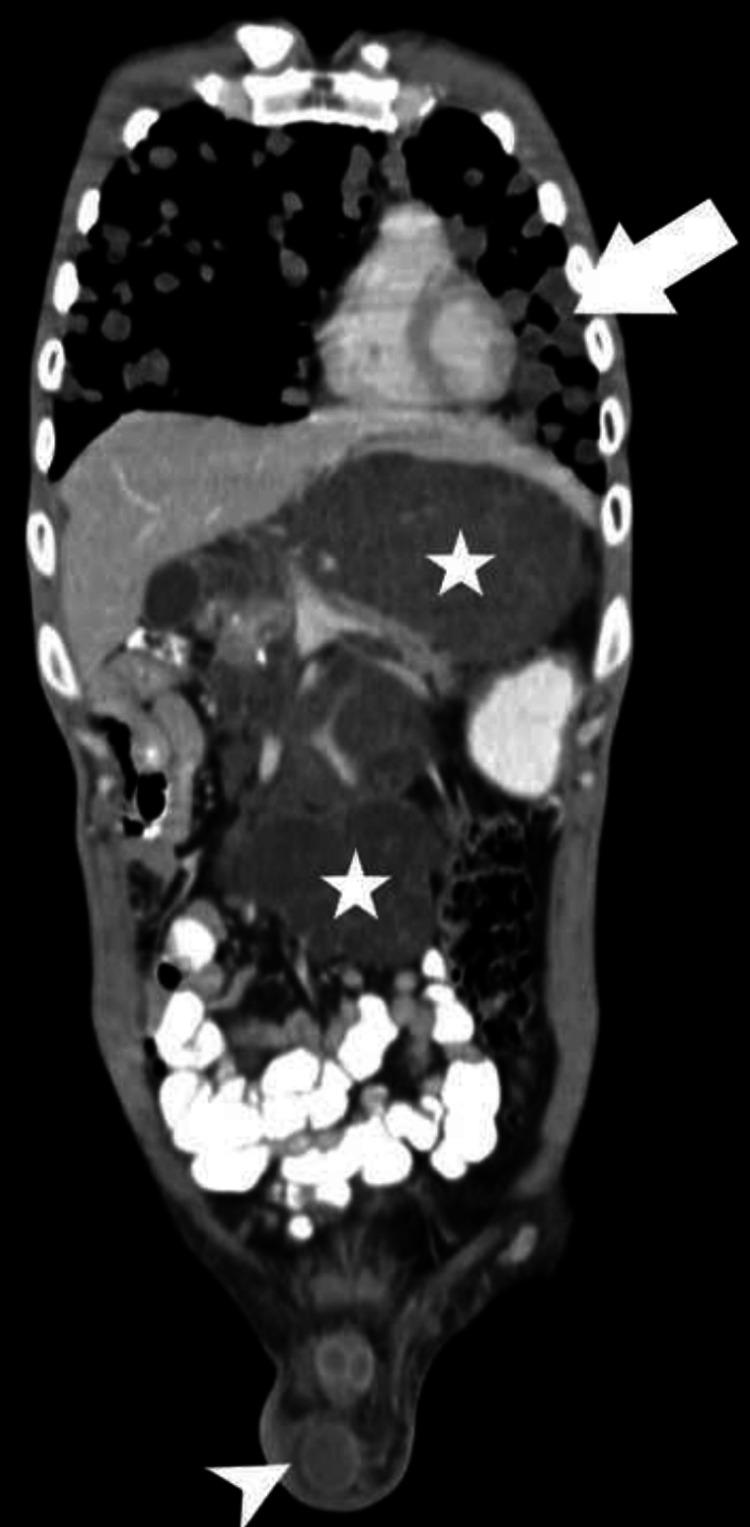

Growing teratoma syndrome (GTS) represents a rare yet significant complication following treatment for non-seminomatous germ cell tumors (NSGCT), characterized by the growth of mature teratoma elements despite prior chemotherapy. We present the case of a 30-year-old male who, following orchidectomy for NSGCT and subsequent chemotherapy, developed acute abdominal pain and pulmonary metastasis. Despite normal serum tumor markers, imaging revealed a large retroperitoneal mass encasing significant vessels. Surgical excision led to symptom resolution. This case underscores the diagnostic challenges GTS poses, the importance of imaging in diagnosis, and the efficacy of prompt surgical intervention in achieving favorable outcomes.

成熟性畸胎瘤综合征(GTS)是非精原细胞性生殖细胞肿瘤(NSGCT)治疗后一种罕见但严重的并发症,其特征是尽管先前进行了化疗,但仍有成熟畸胎瘤成分生长。我们报告了一例30岁男性病例,该患者因NSGCT接受睾丸切除术后并进行了后续化疗,出现了急性腹痛和肺转移。尽管血清肿瘤标志物正常,但影像学检查显示一个巨大的腹膜后肿块包绕了重要血管。手术切除后症状得以缓解。该病例强调了GTS带来的诊断挑战、影像学在诊断中的重要性以及及时手术干预在取得良好预后方面的有效性。